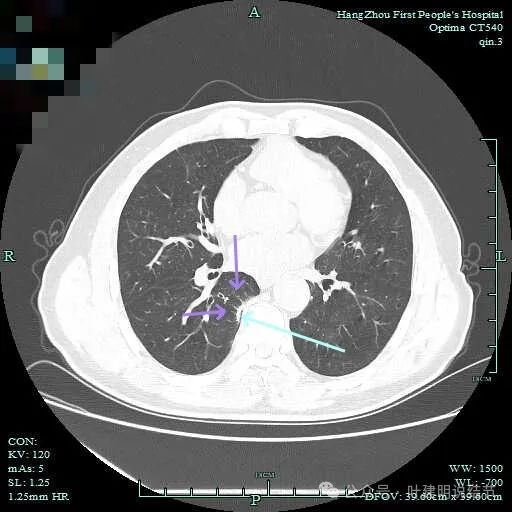

实性密度,片状,条状。

病灶实性,缺乏膨胀性。

上图呈结节状,表面不平,有少许磨玻璃成分。

结节状,密度高,边缘欠光滑。

与脊柱之间有间隙,表面有细毛刺。

表面不平,似有细支气管截断征。

边缘不平毛糙。

像慢性炎似的。

瘤肺边界欠清。

边缘区淡磨玻璃密度。